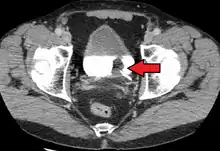

Stage N1 bladder cancer

Advanced bladder cancer (M1b)

Lymph nodes in the pelvis. Bladder cancer commonly spreads to obturator and internal iliac (not labelled)

The most common sites for bladder cancer metastases are the lymph nodes, bones, lung, liver, and peritoneum.[78] The most common sentinel lymph nodes draining bladder cancer are obturator and internal iliac lymph nodes. The location of lymphatic spread depends on the location of the tumors. Tumors on the superolateral bladder wall spread to external iliac lymph nodes. Tumors on the neck, anterior wall and fundus spread commonly to the internal iliac lymph nodes.[79] From the regional lymph nodes (i.e. obturator, internal and external lymph nodes) the cancer spreads to distant sites like the common iliac lymph nodes and paraaortic lymph nodes.[80] Skipped lymph node lesions are not seen in bladder cancer.[79]